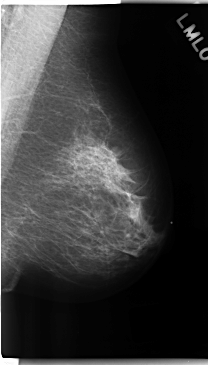

ics_version 1.0 filename C-0225-1 DATE_OF_STUDY 19 3 1997 PATIENT_AGE 55 FILM FILM_TYPE REGULAR DENSITY 2 DATE_DIGITIZED 14 4 1998 DIGITIZER LUMISYS LASER SEQUENCE LEFT_CC LINES 4744 PIXELS_PER_LINE 2512 BITS_PER_PIXEL 12 RESOLUTION 50 NON_OVERLAY LEFT_MLO LINES 4744 PIXELS_PER_LINE 2696 BITS_PER_PIXEL 12 RESOLUTION 50 NON_OVERLAY RIGHT_CC LINES 4736 PIXELS_PER_LINE 2728 BITS_PER_PIXEL 12 RESOLUTION 50 OVERLAY RIGHT_MLO LINES 4736 PIXELS_PER_LINE 2712 BITS_PER_PIXEL 12 RESOLUTION 50 OVERLAY |